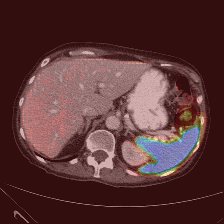

| (a) Ground Truth | (b) Prediction | (c) Heatmap |

In this thorough comparison with top-tier models, our methodology underscores its superiority. To emphasize, the Dice Similarity Coefficient (DSC) of our proposal impressively settles at 82.16%, outclassing formidable contenders like the HiFormer, which rests at 80.39%.

A salient feature of our model is its aptitude for delineating finer anatomical structures. The integration of ISIM markedly amplifies this capability. This prowess is evident in the Gallbladder’s segmentation, where our technique delivers a 71.48% score, overtaking others like the TransDeepLab’s 69.16%. Similarly, the Pancreas, a traditionally intricate organ to segment due to its size, witnesses a conspicuous uplift with our method, achieving 65.02%, surpassing even the FFUNet-trans’s 64.17%.

In the segmentation of more pronounced organs, our model remains unparalleled. The Kidney (L) and Kidney (R) respectively logged scores of 85.45% and 80.85%. Noteworthy is the Liver’s segmentation, where our approach, with a score of 94.85%, nearly mirrors the HiFormer’s 94.61%. Furthermore, in segmenting the Spleen, our model, at 91.62%, slightly edges out our own baseline, which clocked 91.05%.

Reinforcing our point on the model’s capability to harness long-range information, it’s imperative to note our method’s adeptness in segmenting both small and large organs. This demands a considerable receptive field size for precision in object prediction. We further elucidate this with a class activation map for both organ types in Figure 4, shedding light on our model’s enhanced ability to discern local patterns, resulting in meticulous segmentation.